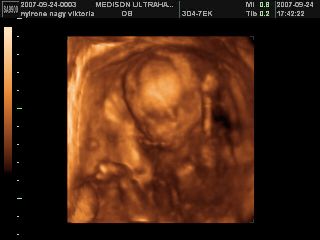

Na megjöttünk az uh-ról, 17 órára volt időpontunk, de majd fél órát csúszott a dolog, mert a doki később tudott bejönni! Minden rendben van, mindene magvan, annyi, amennyinek lennie kell, normál a szíve, a vesék rendben, gyomortelítődés van, méhlepény a fundusban, köldökzsinór 3 erű, viszont nem igen látszott, hogy milyen nemű! A doki szerint inkább lány, mint fiú, de egyáltalán nem mondta egyértelműre, és nem is látszott, összeszorította a lábacskáit a kis szégyenlős! :lol: De a lényeg az, hogy egészséges, és végre láttam az arcát is! :D